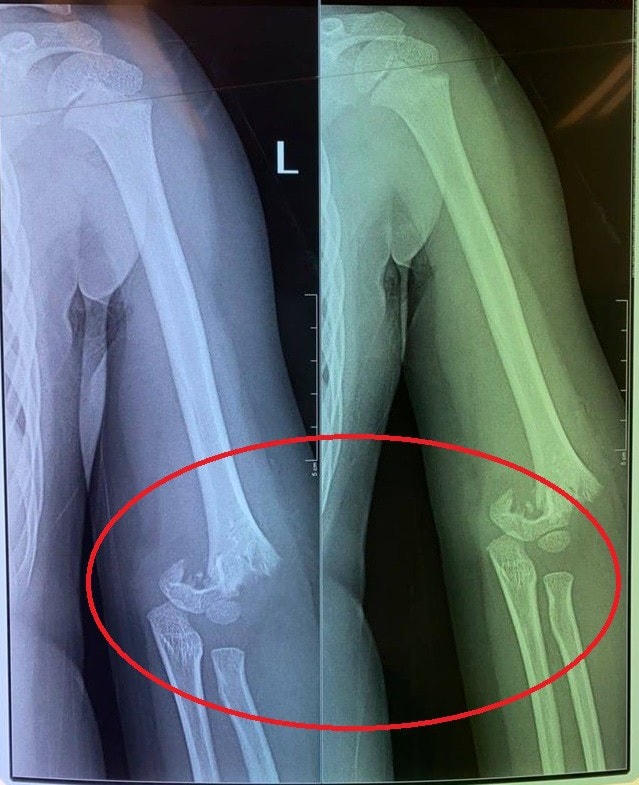

Khi cô giáo thông báo gia đình vào làm thủ tục nhập viện, chị H. bị sốc khi biết con phải mổ cấp cứu, có nguy cơ bị liệt và xem phim chụp XQ thấy xương ở khuỷu tay bị gãy lìa.